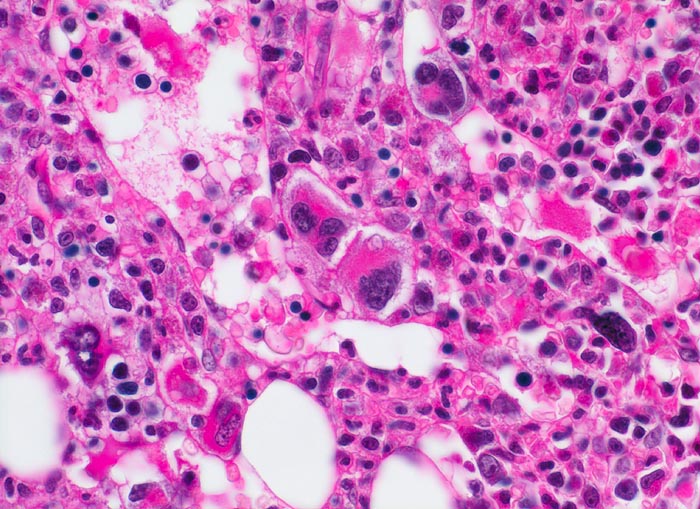

PathoPic – image database / PathoPic ID 3914 - Primäre Myelofibrose (PMF)

Primäre Myelofibrose (PMF)

Knochenmark, Beckenkamm

Neben atypischen, teils nacktkernigen Megakaryozyten zahlreiche Erythropoeseherde und myeloische Zellen verschiedener Reifungsstufen. Die Hämopoese ist auch in den dilatierten Markgefässen nachweisbar.

Splenomegalie, leichte Anämie, Leukozytose und Thrombozytose festgestellt bei einer Routineuntersuchung bei asymptomatischer Patientin.

Histologie

400